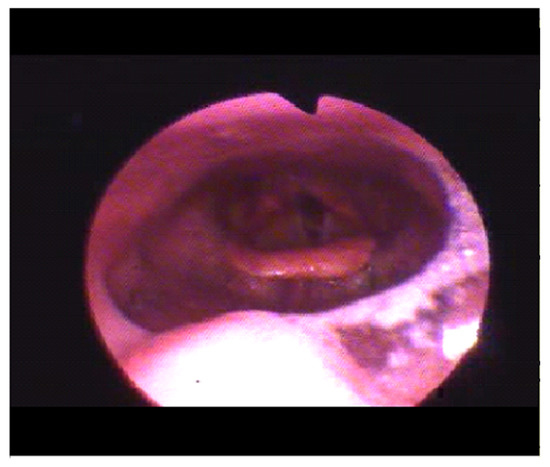

An average BIS value of 45, a minimum of 25, an average SPO2 of 85 and a minimum of 76 are reported. In the male patient, we observed a retropalatal oropharyngeal obstruction site with 100% concentric prolapse and a retrolingual oropharyngeal obstruction site with 75% concentric prolapse. The average 65 and minimum 49 BIS values are reported, and the SPO2 values were 89% the average and 85% the minimum (Figure 4).

Figure 4. The figure shows the presence of obstructive apnea based on respiratory parameters (PNG1, PNG2, PNG3), with associated desaturation (87–89% range) and increased muscles activities on PNG4 (mylohyoid muscle), EMG1 (right masseter muscle) and EMG2 (left masseter muscle).